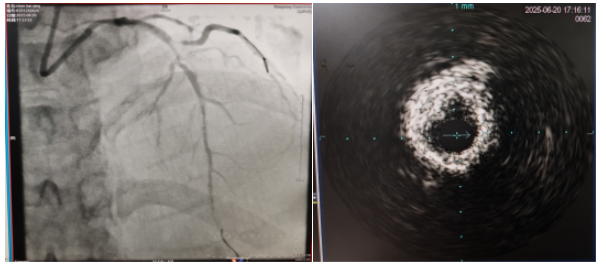

術(shù)中,趙慶禧主任醫(yī)師、雷剛副主任醫(yī)師運(yùn)用IVUS血管內(nèi)超聲技術(shù)評(píng)估,發(fā)現(xiàn)患者前降支、對(duì)角支0.1.1型真性分叉病變,前降支近中段嚴(yán)重鈣化、成角并99%狹窄,對(duì)角支近段嚴(yán)重鈣化并99%狹窄,傳統(tǒng)冠狀動(dòng)脈旋磨術(shù)容易引起冠狀動(dòng)脈穿孔,決定采用沖擊波球囊技術(shù)即血管內(nèi)沖擊波鈣化碎裂術(shù)對(duì)患者嚴(yán)重鈣化的血管進(jìn)行介入治療。通過(guò)球囊低壓擴(kuò)張,向血管病變處發(fā)射非聚焦、低能量、脈沖式的沖擊波,對(duì)前降支及對(duì)角支進(jìn)行了連續(xù)5個(gè)周期沖擊波脈沖治療,安全地碎裂淺、深層鈣化,原本看似堅(jiān)不可摧的環(huán)形鈣化區(qū)逐漸顯現(xiàn)出了裂痕,多處關(guān)鍵位置發(fā)生了斷裂,充分預(yù)處理后于前降支近中段串聯(lián)植入支架3枚,對(duì)角支植入藥物球囊,術(shù)后造影見血管病變處狹窄完全消失,支架膨脹完全,貼壁良好,各項(xiàng)生命體征平穩(wěn),手術(shù)非常成功,患者返回心血管內(nèi)科病房繼續(xù)治療,并于4天后順利出院。